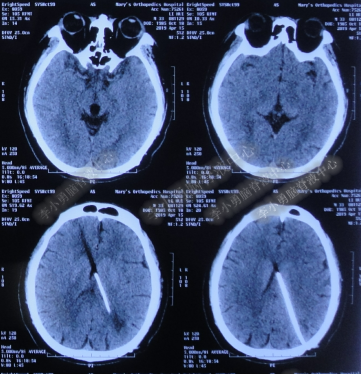

2016年5月9日因“间断性眩晕半月,恶心呕吐一周”以“梗阻性”脑积水,第1次住入北京某企业三级医院神经外科内镜组。2016年5月10日(入院后第2天)行头部MRI(图-1)检查示脑室系统扩张。

图-1:2016年5月10日头部MR